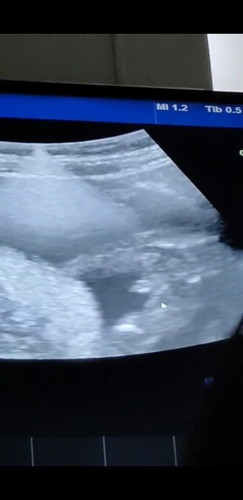

บ้านนี้ชายแน่นอน ตั้งแต่ 12 weeks เห็นชัดแบบไม่ต้องซูม

คุณหมอบอก ผช ล้านเปอร์ค่ะแม่😂

21 eek แล้วค่ะแม่🥰

ผู้ชายค่ะ